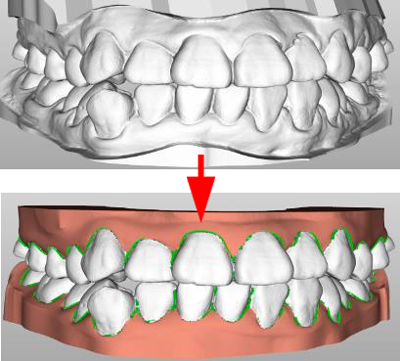

• 以人工智慧為基礎的牙齒分離&分析技術

Auto tooth separation   Auto tooth axis   Auto simulator for tooh alignment

Before After